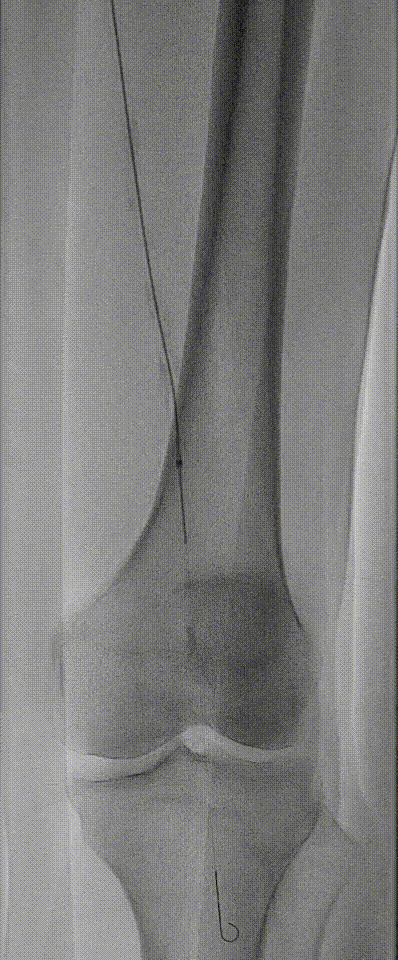

图:造影及通过病变

图:IVUS确认

图:Jetstream 应用

图:DCB 5-250 扩张及全程造影